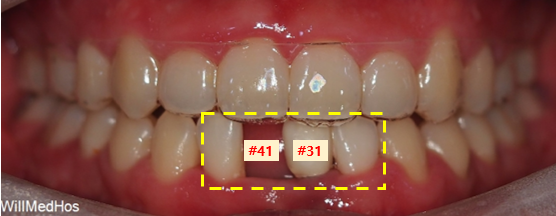

▲초진 구강 사진 ▲초진 파노라마사진

#41 치아는 원래 없으신 상태로#42 치아는 픽스쳐까지 있는 상태로 오셨습니다.

(투명한 장치는 교정 이후 투명 유지 장치입니다.)